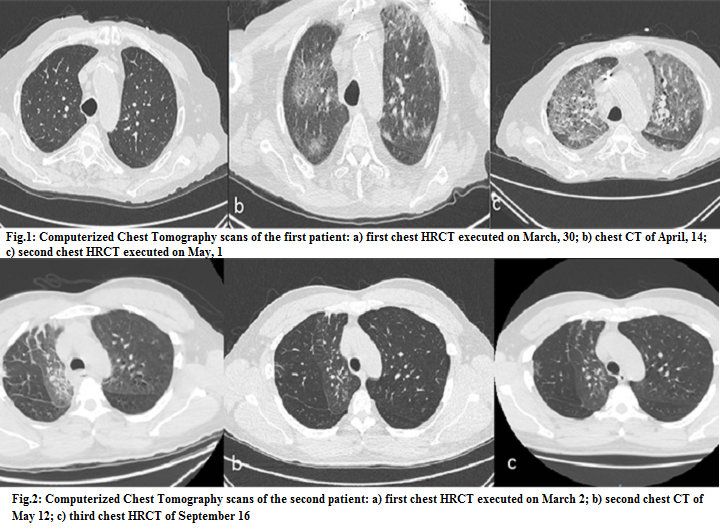

Open AccessCase Series

SARS-CoV-2 Reinfection: Two Different Possible Presentations of Disease. Our Experience in a Province of Northern Italy

Fabbri Nicolò, Greco Salvatore

International Journal of Innovative Research in Medical Science·October 18, 2020